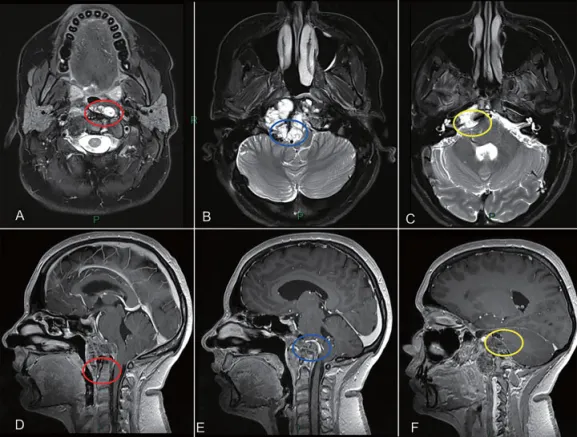

图2:颅颈交界区肿瘤手术治疗策略分析,肿瘤的旁正中部分可以通过经鼻内镜手术切除。枢椎齿状突周边肿瘤(A和D处红色圆圈)、侵犯硬膜内部分的肿瘤与后循环接触(B和E处蓝色圆圈)和先前乙状窦后入路手术的粘连(C和F处黄色圆圈),这些部位的肿瘤更适合二期远外侧开颅手术。